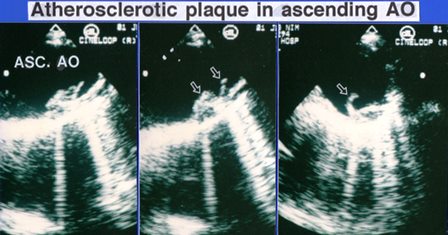

경식도 심장초음파로 관찰한 대동맥 내벽에 붙은 동맥경화반이다.일부는 실타래처럼 움직였다.